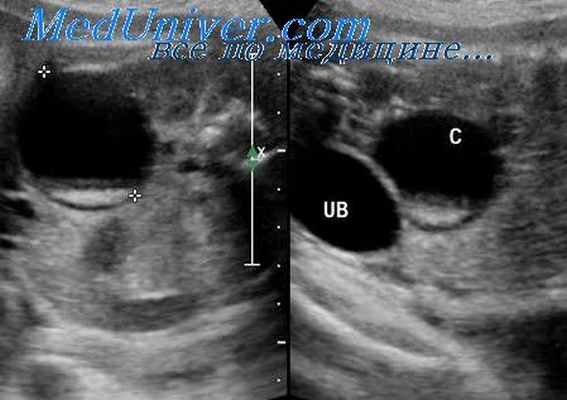

Неопущение яичка (крипторхизм) может быть выявлено при ультразвуковом исследовании по отсутствию возможности визуализировать яичко в мошонке. Поскольку яички полностью опускаются в мошонку только на поздних сроках беременности, в первой половине третьего триместра это состояние может обнаруживаться по меньшей мере у 10% плодов.

К концу беременности частота неопущения яичек уменьшается до 0,7%. Хотя в большинстве случаев крипторхизм встречается изолированно, он также может встречаться при целом ряде других синдромов, в том числе при синдроме недостаточности мышц живота (синдроме prune-belly), синдроме Нунан (Noonan) и трисомиях 13, 18 и 21.

- Ультрасонографии органов малого таза (УЗИ) и р ентгенологическое обследование для выяснения состояния органов малого таза . В малом тазу не визуализируется матка и яичники. Забрюшинно визуализируются образования, похожие на "яичники", на самом деле это яички (без дополнительных данных анамнеза бывает трудно это предположить). Мужские гонады могут располагаться в паховых каналах, в стенках таза или в толще больших половых губ.